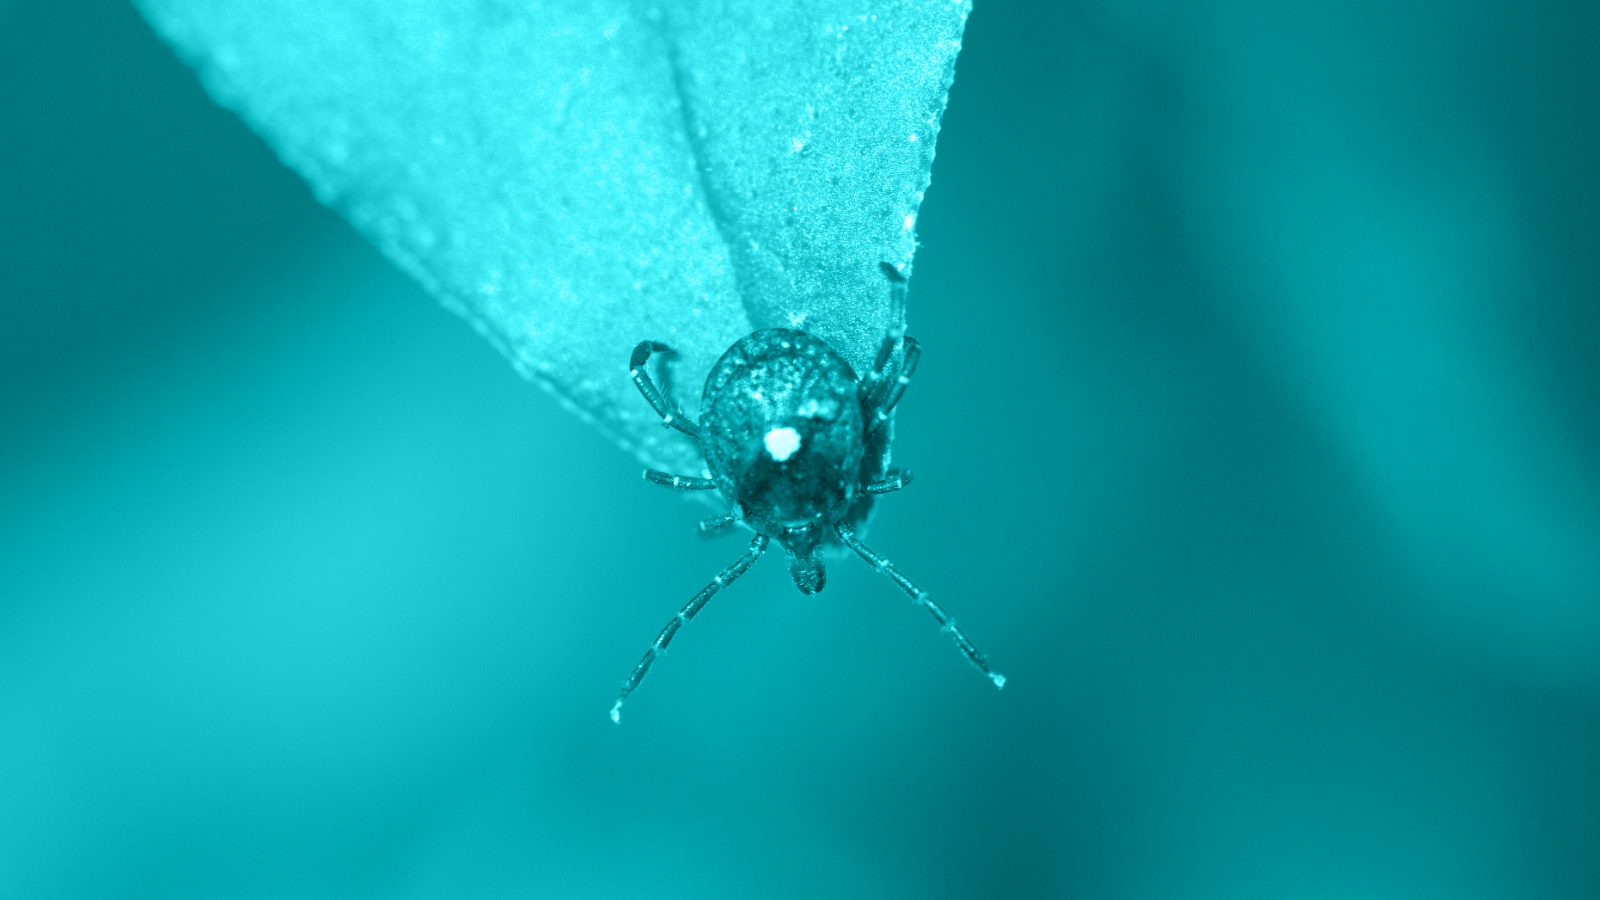

New World screwworm cases rise to 9 as FDA emergency authorizes OTC treatment for pets, plus the launch of a generic for congestive heart failure in dogs.

Generic Nitenpyram Tablets become the first generic animal drug authorized under an FDA Emergency Use Authorization to treat New World screwworm myiasis in eligible dogs, cats, puppies, and kittens.

What modern parasite prevention actually built—and what complacency could quietly dismantle.

A list of available treatments for screwworm infestations in cattle, horses, sheep, goats, deer, swine, cats, dogs, exotic, zoo, and wildlife species, as well as guidance for practitioners before using these products.

New World screwworm confirmed in New Mexico dog as US case count rises to 5

Federal officials have confirmed additional New World screwworm detections in Texas and New Mexico, bringing the total to 5 cases in 6 days, including the first in a companion animal since the parasite’s return to the United States.

Christopher Lee, DVM, MPH, DACVPM, DACVM (Parasitology), on why the NWS detection in Texas signals something far bigger—and what clinicians need to do now. Plus: early warning signs, identification, lab submission, and risk to pets.